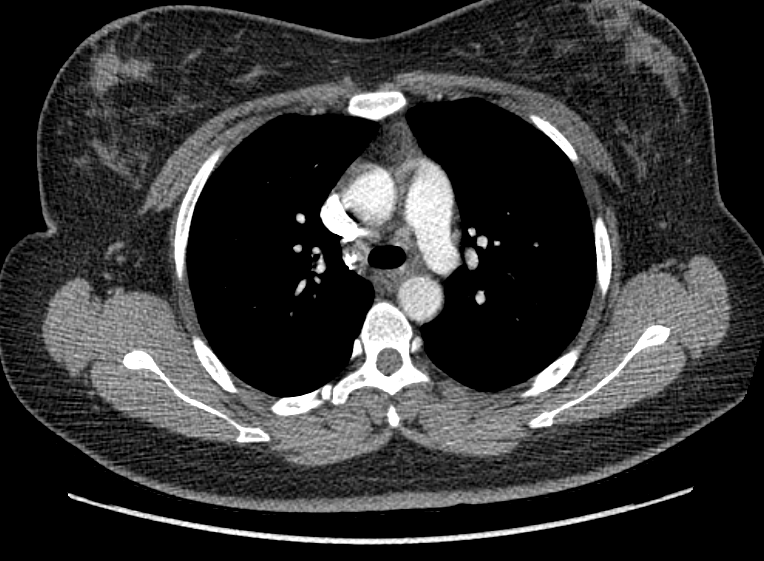

F/34

°Ç°­°ËÁø»ó ½ÃÇàÇÑ Chest PA »ó mediastinal widening ¼Ò°ßÀ¸·Î further evaluation À§ÇØ ³»¿øÇÔ.

Áõ»óÈ£¼Ò ¾øÀ¸¸ç ½Åü°ËÁø»ó ƯÀÌ¼Ò°ß ¾øÀ½.